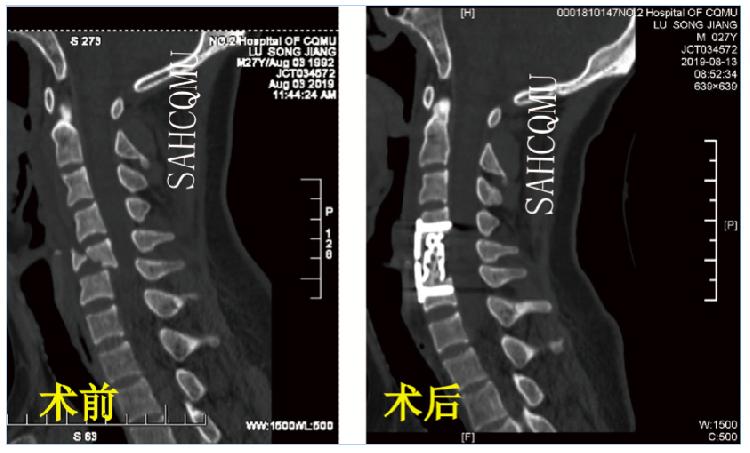

(C5 ACCF手术·术前术后对比)

颈椎前路手术即:从颈部前方做切口,牵拉开气管和食管,从椎体前方对椎管进行减压,包括:颈椎前路椎间盘切除减压植骨融合术(ACDF)、颈椎前路椎体次全切除减压植骨融合术(ACCF),或者两种术式相结合的杂交手术。主要适用于前柱结构损伤为主的患者,特别是有椎间盘损伤突出压迫脊髓者,其优势在于能彻底的减压以及更加确切的融合。